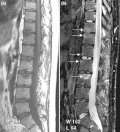

(a) STIR Sagittal MRI of ankle showing enthesitis at Achilles tendon insertion (thick arrow), synovitis of ankle joint (long thin arrow), and bone marrow edema at tendon insertion (short thin arrow). T1-weighted images, before (b) and after (c) contrast, show enthesitis (large arrow) and bone erosion at tendon insertion (short thin arrows).